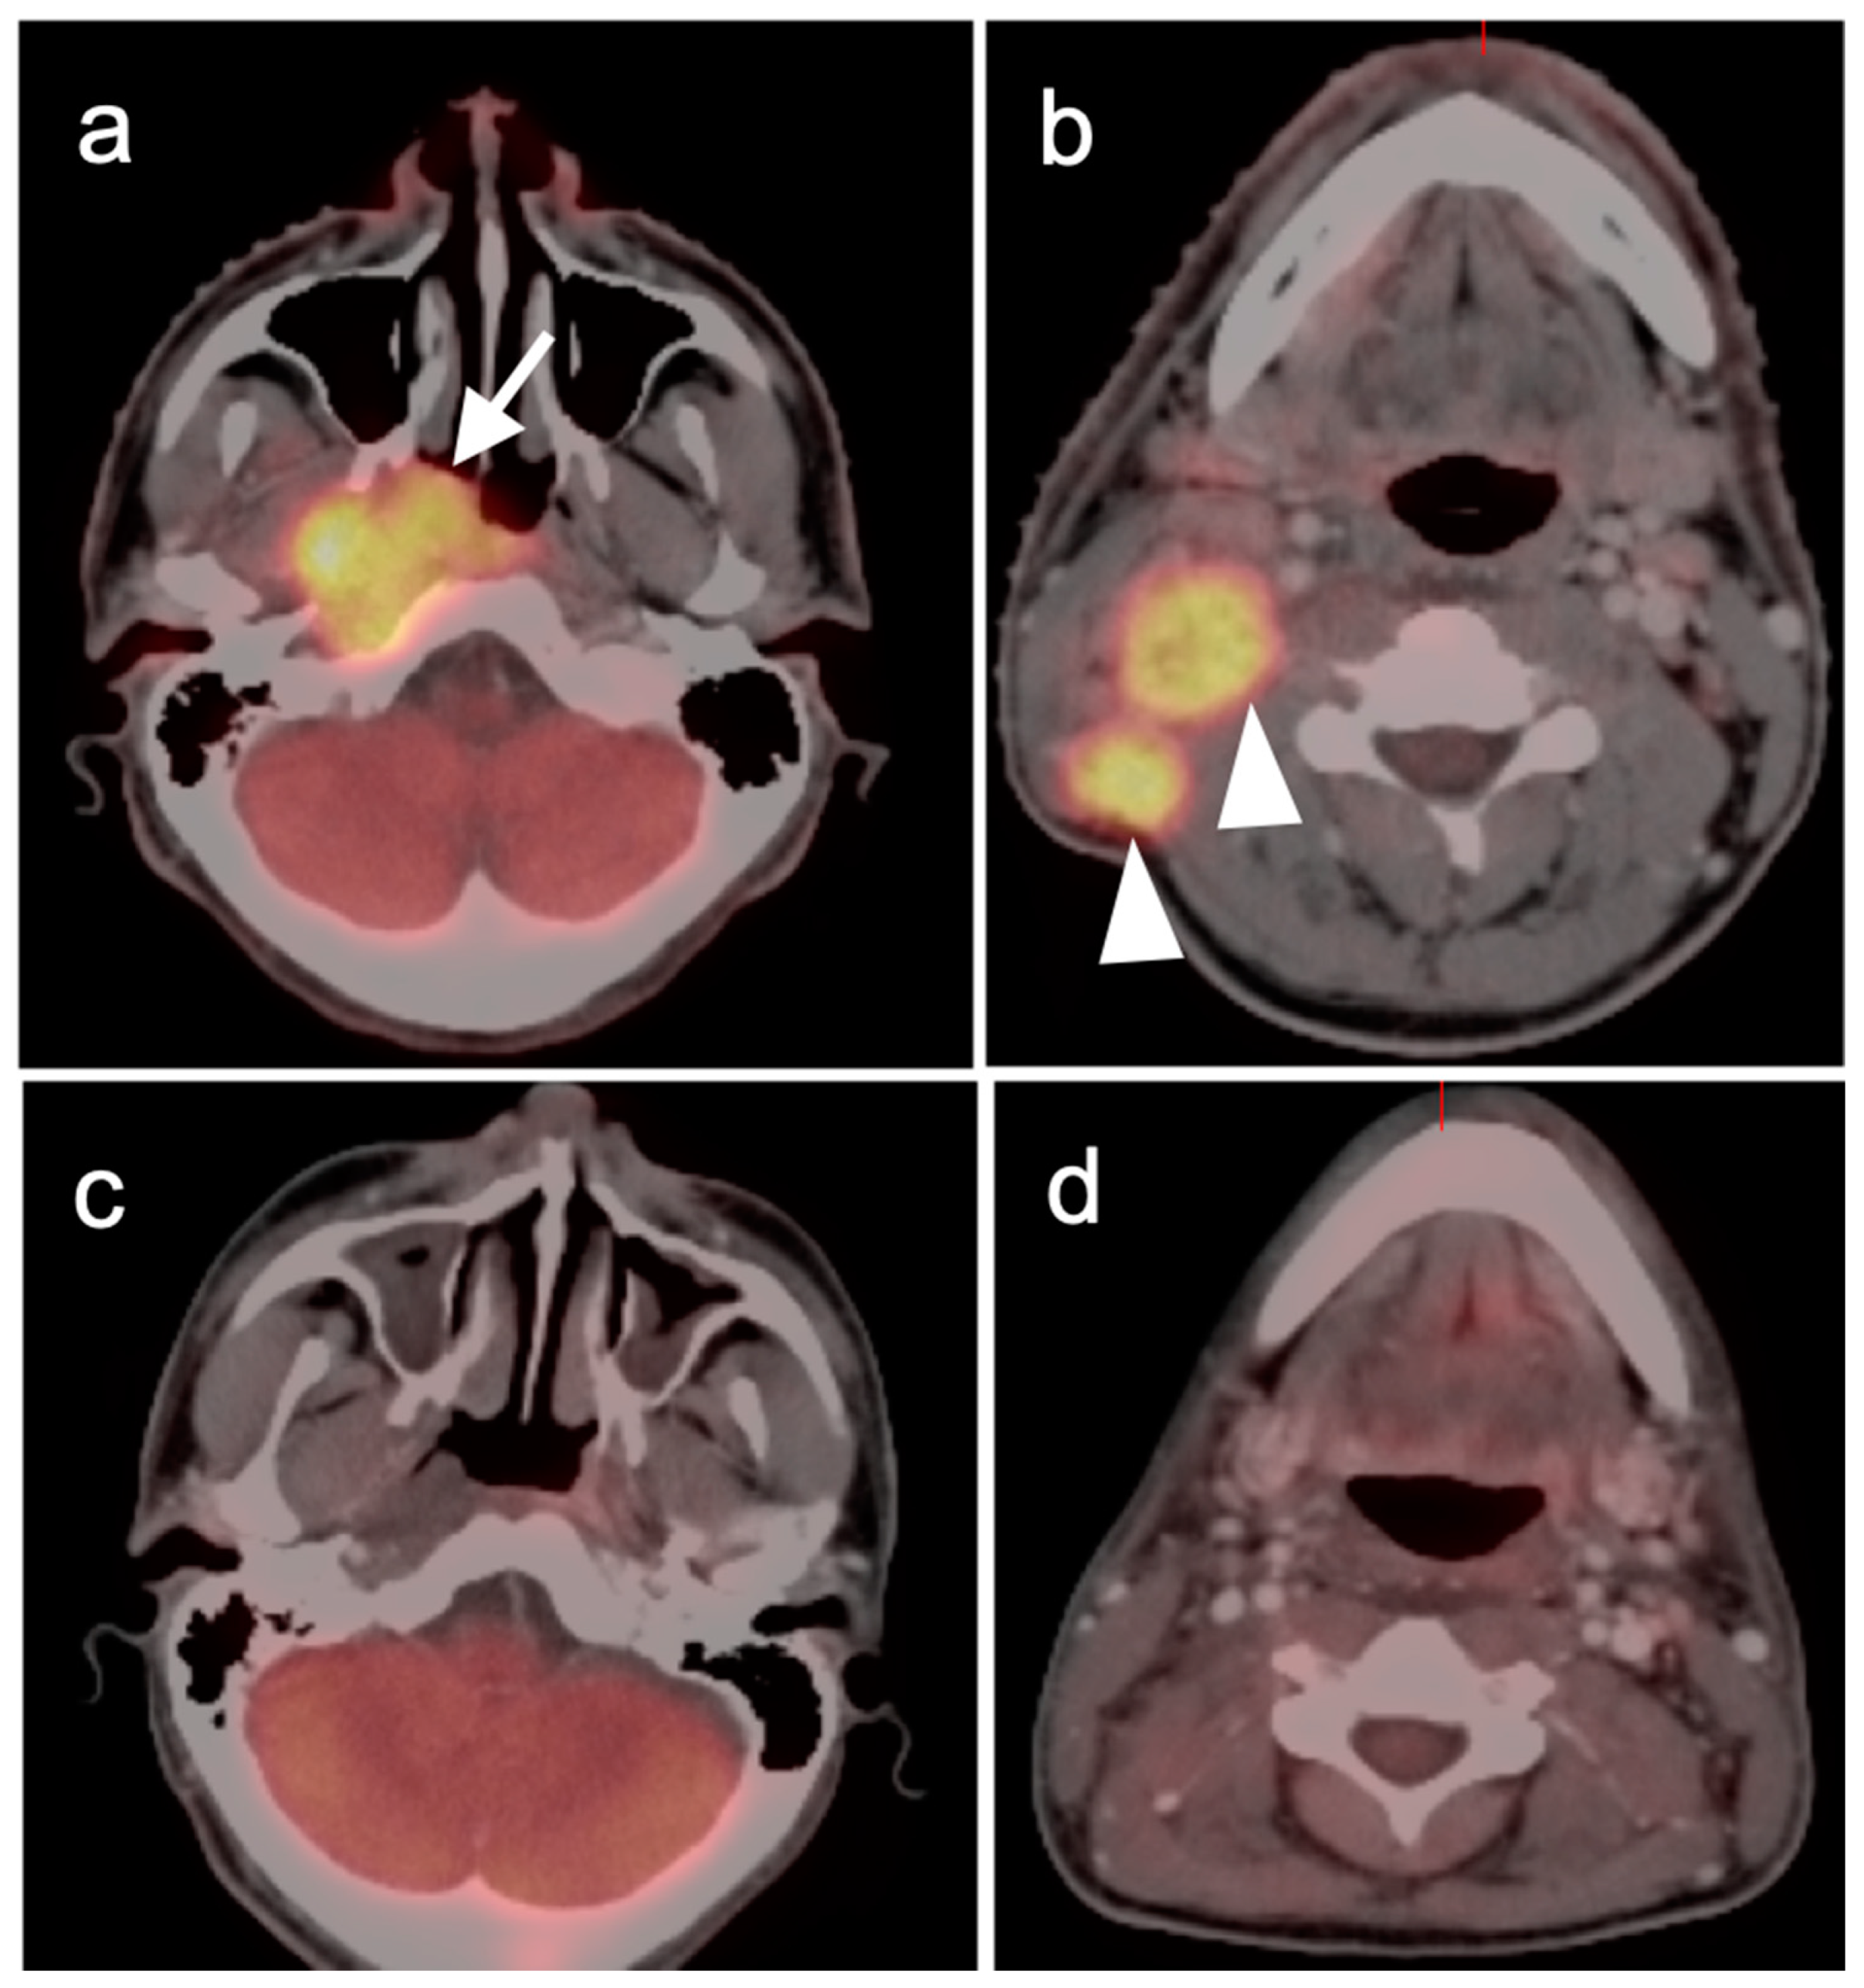

2.3. Nasopharyngeal Carcinoma

2.4. Sinonasal Tumors

3.2. Paraneoplastic CNS Manifestations and Sources of False Positive FDG PET Scans That Can Mimic Brain Tumors

3.3. Primary Brain Tumors

3.4. CNS Lymphoma

3.5. Brain Metastases